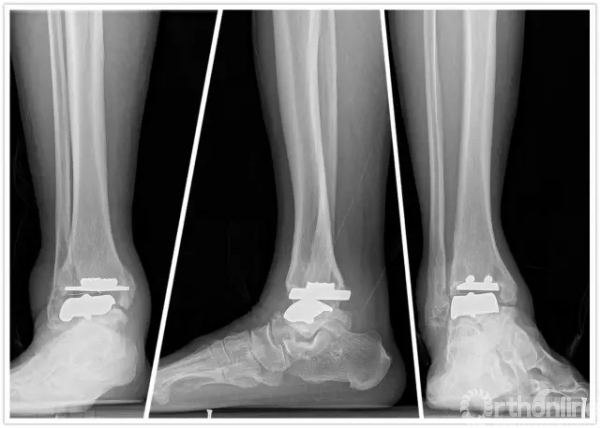

方老伯,今年67岁,20067月他因左侧踝关节严重骨关节炎到上海瑞金医院就诊,当时刘津浩副主任考虑其踝关节和距下关节都已经出现严重的骨关节炎,无法保留关节,于是对其进行了胫距跟双关节融合手术。手术后方老伯恢复良好,如期达到骨性融合。2年后,方老伯右侧踝关节开始出现肿胀疼痛,日夜反复发作,直到20102月,他无法忍受,再来医院就诊,拍片后发现他右侧踝关节也出现明显骨关节炎。此时正值瑞金医院足踝外科全面发展时期,足踝外科的新理念、新技术已经引入瑞金医院,当时学科带头人徐向阳主任认为该患者左侧踝关节已经行融合手术,右侧不适宜再行融合手术。于是徐主任主刀、刘津浩副主任和朱渊医师担任助手,顺利为方老伯进行了踝关节STAR假体置换术,手术后保持随访康复良好,又恢复了往常的劳作。

直到1年前,方老伯感觉右侧踝关节又开始出现肿胀疼痛,劳作后加重,最近越来越重。20167月再来徐主任门诊复查,徐主任考虑踝关节假体出现了松动,距骨有了塌陷,关节力线有所偏移。鉴于目前瑞金医院足踝外科已经开展踝关节INBONE假体置换术,积累了一定的经验,于是徐主任向患者及家属解释病情,建议再行踝关节翻修术。